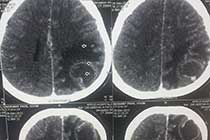

Brain Abscess Brain Abscess Post OP 2 Clinical Intra OP ,After Excising The Granuloma Intaop Scalp Abscess CT Scalp Abscess Cerebellar Abscess Post OP Clinical Cerebellar Abscess Brain TB Granuloma Post OP CT Scan Brain Infection Brain Abscess Preop MRI 2 Brain Abscess PRE OP Clinical 1 Brain Abscess PRE OP Brain Abscess Intraop 2 Brain Abscess Following Shunt Temporal Abscess T2W of TB Granuloma Scalp Abscess Preop CT Marking PRW OP MRI of TB Granuloma Post OP Clinical Photo Post OP Cerebellar Abscess Post OP Brain Abscess Intraop Specimen of Granuloma